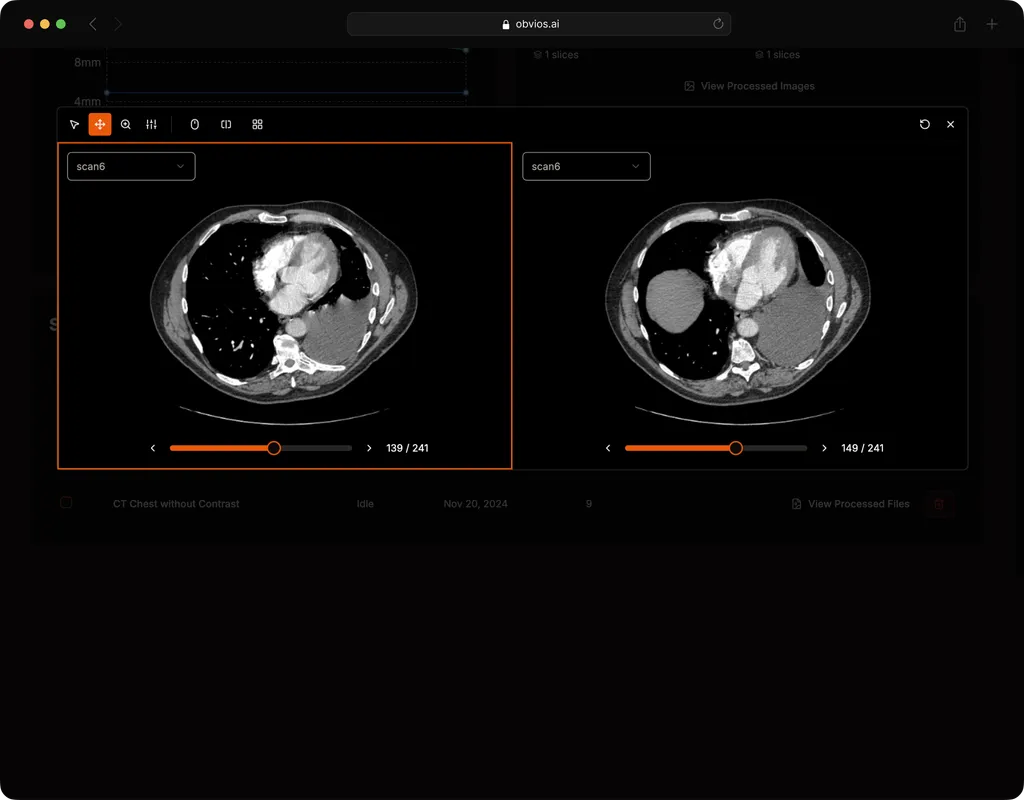

Lung Nodule Detection and Tracing Across Scans

Obvios.ai utilizes cutting-edge artificial intelligence to meticulously detect and track lung nodules, facilitating swift and precise diagnostics, thereby ensuring superior care and timely intervention for patients.